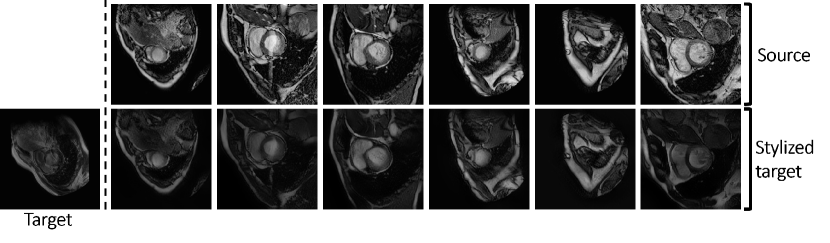

Figure 2: Qualitative results of RAIN on bSSFP \rightarrow LGE. The first column shows a LGE axial slice as the style image. The first row shows the bSSFP images as the content images, the second row shows the corresponding stylized LGE images.

Fig. 2 shows the qualitative results of the pretrained RAIN. We can observe that RAIN successfully captures the features of target images. Tab. 1 summarizes the quantitative results of different methods. Baseline method achieved the lowest average volumetric Dice (0.30) and an HD (35.9\tsmm). With a few-shot UDA setting, our proposed method achieved the best overall Dice (0.63) and the best lowest HD (20.2\tsmm). Subsequently, we demonstrate the results for one-shot UDA, and our proposed method achieved the highest Dice (0.58) and the lowest HD (26.9\tsmm). Fig. 3 illustrates qualitative examples of different segmentation approaches. Compared with other methods, the proposed method is able to produce more complete and precise segmentation maps.